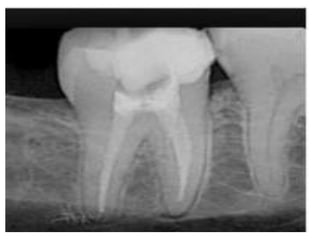

In initial stages,periapical granuloma show widening

of the

periodontal ligament space of the tooth.

Fully developed lesions usually produce a well

defined

radiolucent area of varying size which appears to be

in continuity with the root apex.

Long standing periapical granuloma may show

varying

degrees of root resorption.

Radiographical features: In initialstages,periapical granuloma show widening of the periodontal ligament space of the tooth. Fully developed lesions usually produce a well defined radiolucent area of varying size which appears to be in continuity with the root apex. Long standing periapical granuloma may show varying degrees of root resorption.